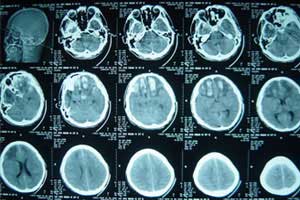

颅底骨折依其发生部位不同,分为颅前窝骨折,颅中窝骨折和颅后窝骨折,临床表现各有特征,兹分述如下(图3)。